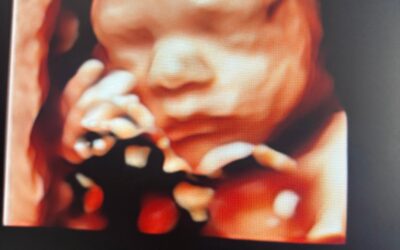

New Sheffield clinic offers earlier baby gender scans for expectant parents

A new baby scan clinic in Sheffield is offering gender scans offering expectant parents the chance to find out their baby’s gender earlier than usual. The Baby Ultra...